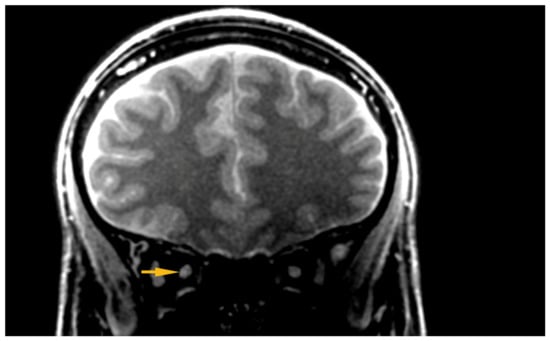

Silent-MT images obtained in a healthy control clearly distinguish the axonal part of the optic nerve and surrounding structures. The optic nerve is clearly visible as well as the surrounding CSF and the optic nerve sheath in the healthy individual. Silent-MT images showed good signal and strong contrast in the optic nerve, had excellent suppression of the fat surrounding the ONSC, and showed no motion artifact. In LHON patients hyperintense areas are visible along the whole optic nerve (Figure 2 and Figure 3). Moreover, the nerve itself looks thinner, with an irregular shape and structure. Abnormalities are mostly visible within the proximal and distal part of the optic nerve as well as within the optic disc area. Moreover, in this work we demonstrate that increasing the number of spokes per group to 192 increases the sequence time efficiency and reduces RF power deposition while maintaining significant MT contrast. There were no adverse events reported in any participant after the scanning.

Figure 2.

Hyper intensive area visible within the ONSC. ONSC, Optic Nerve Sheath Complex.

Current literature does not provide a complete picture about the abnormalities associated with LHON that can be visualized using magnetic resonance imaging. The short tau inversion recovery (STIR) protocol is commonly used for imaging optic nerve disease such as optic neuritis, allowing good depiction of the inflammation within the optic nerve as well as due to its short acquisition time [21]. There are several case reports describing abnormalities in MRI in the anterior optic pathway region. Kermode et al. reported the occurrence of hyperintensities within the posterior part of the optic nerve in 13 subjects [22] and several studies have reported hyperintensities within the anterior part of the optic nerve [23,24,25,26,27,28]. Recent papers, in which high-field magnetic resonance was used, have reported hyperintense areas within the distal parts of the optic nerve, optic chiasm, optic tract, and enlargement of the optic chiasm.

In two cases of LHON, increased signal on T2-weighted scans was seen not only in the optic nerve but also in the optic tracts, extending as far as the lateral geniculate bodies [29,30]. Chiasmal enlargement and optic nerve enhancement was observed in Gadolinium-enhanced T1-weighted imaging in two cases of Leber’s hereditary optic neuropathy [31]. T2-weighted MRI showed hyperintensity in the posterior portion of both optic nerves and in the optic chiasm in 19 of 28 LHON patients, and enlargement of the chiasm was found in 16 patients [32]. In a case of LHON, T2-weighted fluid-attenuated inversion recovery (FLAIR) imaging revealed asymmetrical chiasmal hyperintensities and enlargement and chiasmal enhancement on Gadolinium-enhanced T1-weighted imaging [33].